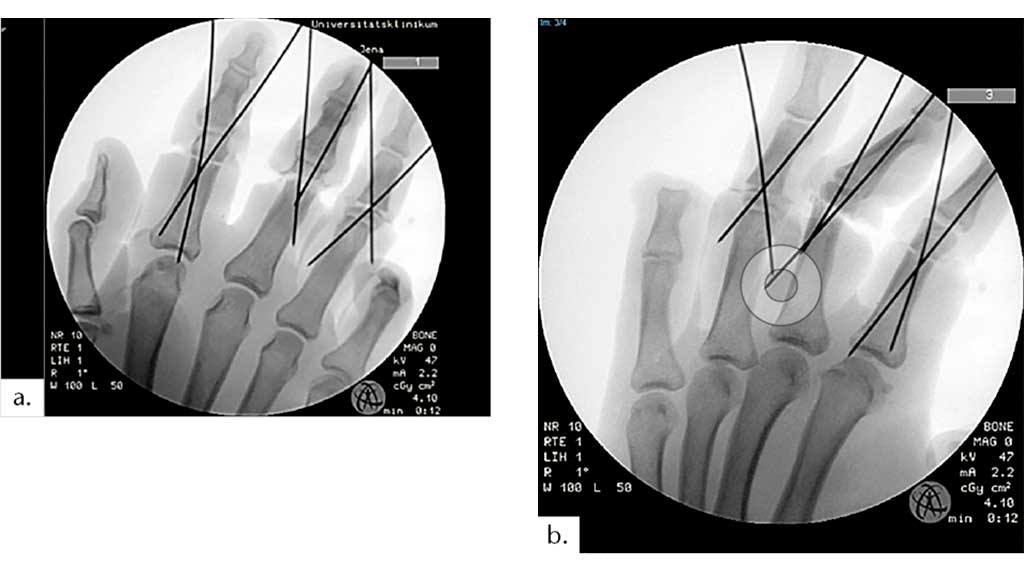

Der 34-jährige männliche Patient zog sich beim Transport einer Blechbearbeitungsmaschine eine traumatische Fingeramputation D II‑V beider Hände zu (Abb. 6a, b). An der rechten Hand zeigte sich eine subtotale Amputation sämtlicher Langfinger auf Höhe der Grundglieder. Es erfolgte die Replantation der Finger 2–5 (Abb. 7a). An der linken Hand kam es zu einer kompletten Abtrennung sämtlicher Langfinger – D2 und D3 auf Höhe des Grundgliedes, D4 auf Höhe des Mittelgliedes, D5 war auf Höhe der Endphalanx amputiert. Es wurden zunächst die Finger D2 und D3 replantiert. Ring- und kleiner Finger der linken Seite mussten mittig der Grundphalanx D4 und der Mittelphalanx D5 amputiert werden (Abb. 7b).